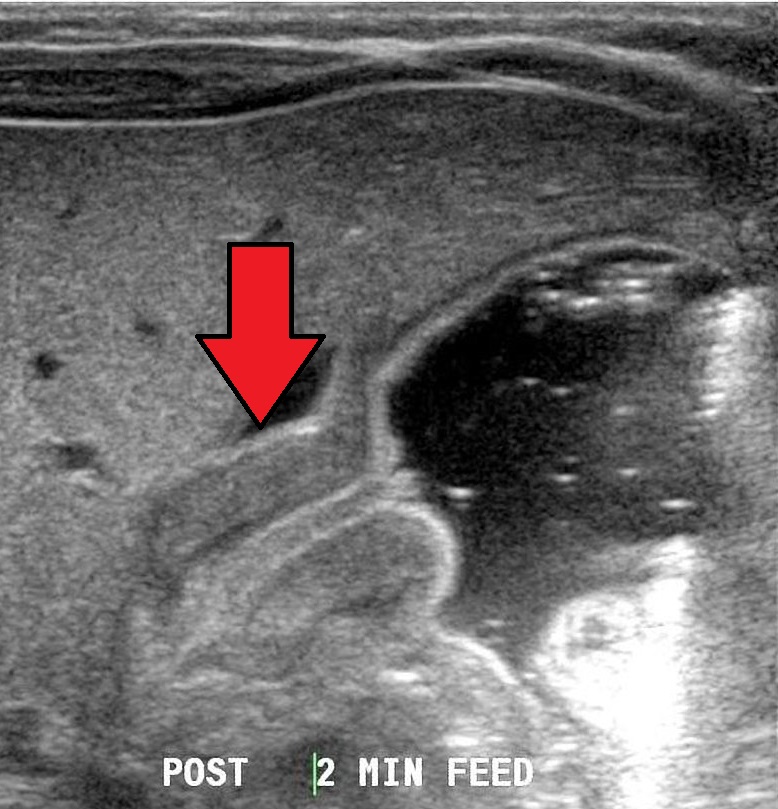

Pyloric Stenosis

A pyloric stenosis is due to congenital hypertrophy of pyloric smooth muscle.

Pyloric stenosis is more common in males.

Pyloric stenosis usually presents two weeks after birth.

Symptoms of pyloric stenosis include:

- Projectile nonbilious vomiting

- Visible peristalsis

- Olive-like mass in the abdomen

Pyloric stenosis is treated by myotomy.

Electrolytes may be necessary to replace what was lost during emesis.